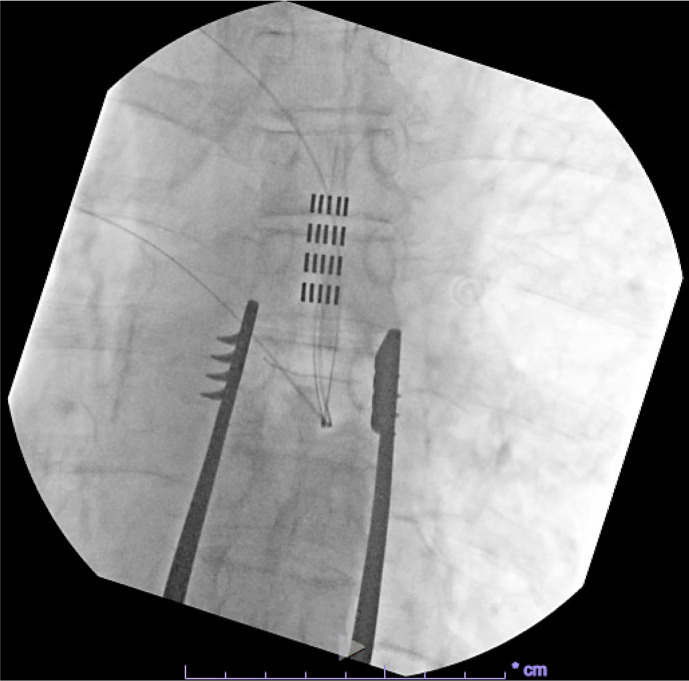

Case presentation: A patient in their 70s presented with a 30-year history of chronic abdominal pain diffusely located in all four quadrants. The patient had a pancreatic cyst removed via pancreaticoduodenectomy in 1991 complicated by chronic pancreatitis and visceral hyperalgesia. After failed pharmacological management and various outpatient nerve blocks and trigger point injections, the patient underwent SCS placement via five 4-contact paddle leads at the mid- to superior thoracic 7 level. At 1-month follow-up, the patient's visual analog scale score decreased from 8/10 (prior to implantation) to 0/10. The patient also discontinued his chronic opioid regimen post-SCS placement but continued duloxetine. Device settings remained the same throughout the postoperative period: pulse width of 500 microseconds (inter-burst) and 1,000 microseconds, frequency of 40 Hertz, and current of 1.7 milliamperes. At 12-month follow-up, the patient continued to report >90% pain relief at nearly the same SCS settings as the initial programming.